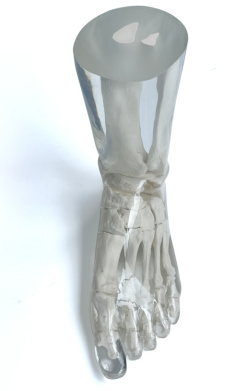

成人腿部模體,用于 X 射線 CT 和超聲波的成人腿部(肌肉)模型是一種基于人類男性腿部平均解剖結(jié)構(gòu)設(shè)計的逼真模型。它具有所有基本的骨骼和

軟組織特征,使其成為學(xué)習(xí)、研究和測試醫(yī)學(xué)成像設(shè)備的理想工具。 模體可用于研究不同方向和定位技術(shù)的多種診斷性 X 射線 CT 和超聲程序。根據(jù)

要求,該產(chǎn)品可以根據(jù)不同的病理進行定制,也可以用于特定的培訓(xùn)應(yīng)用。 模體尺寸:965.2 x 254 x 177.8 毫米,重量:12kg(約)